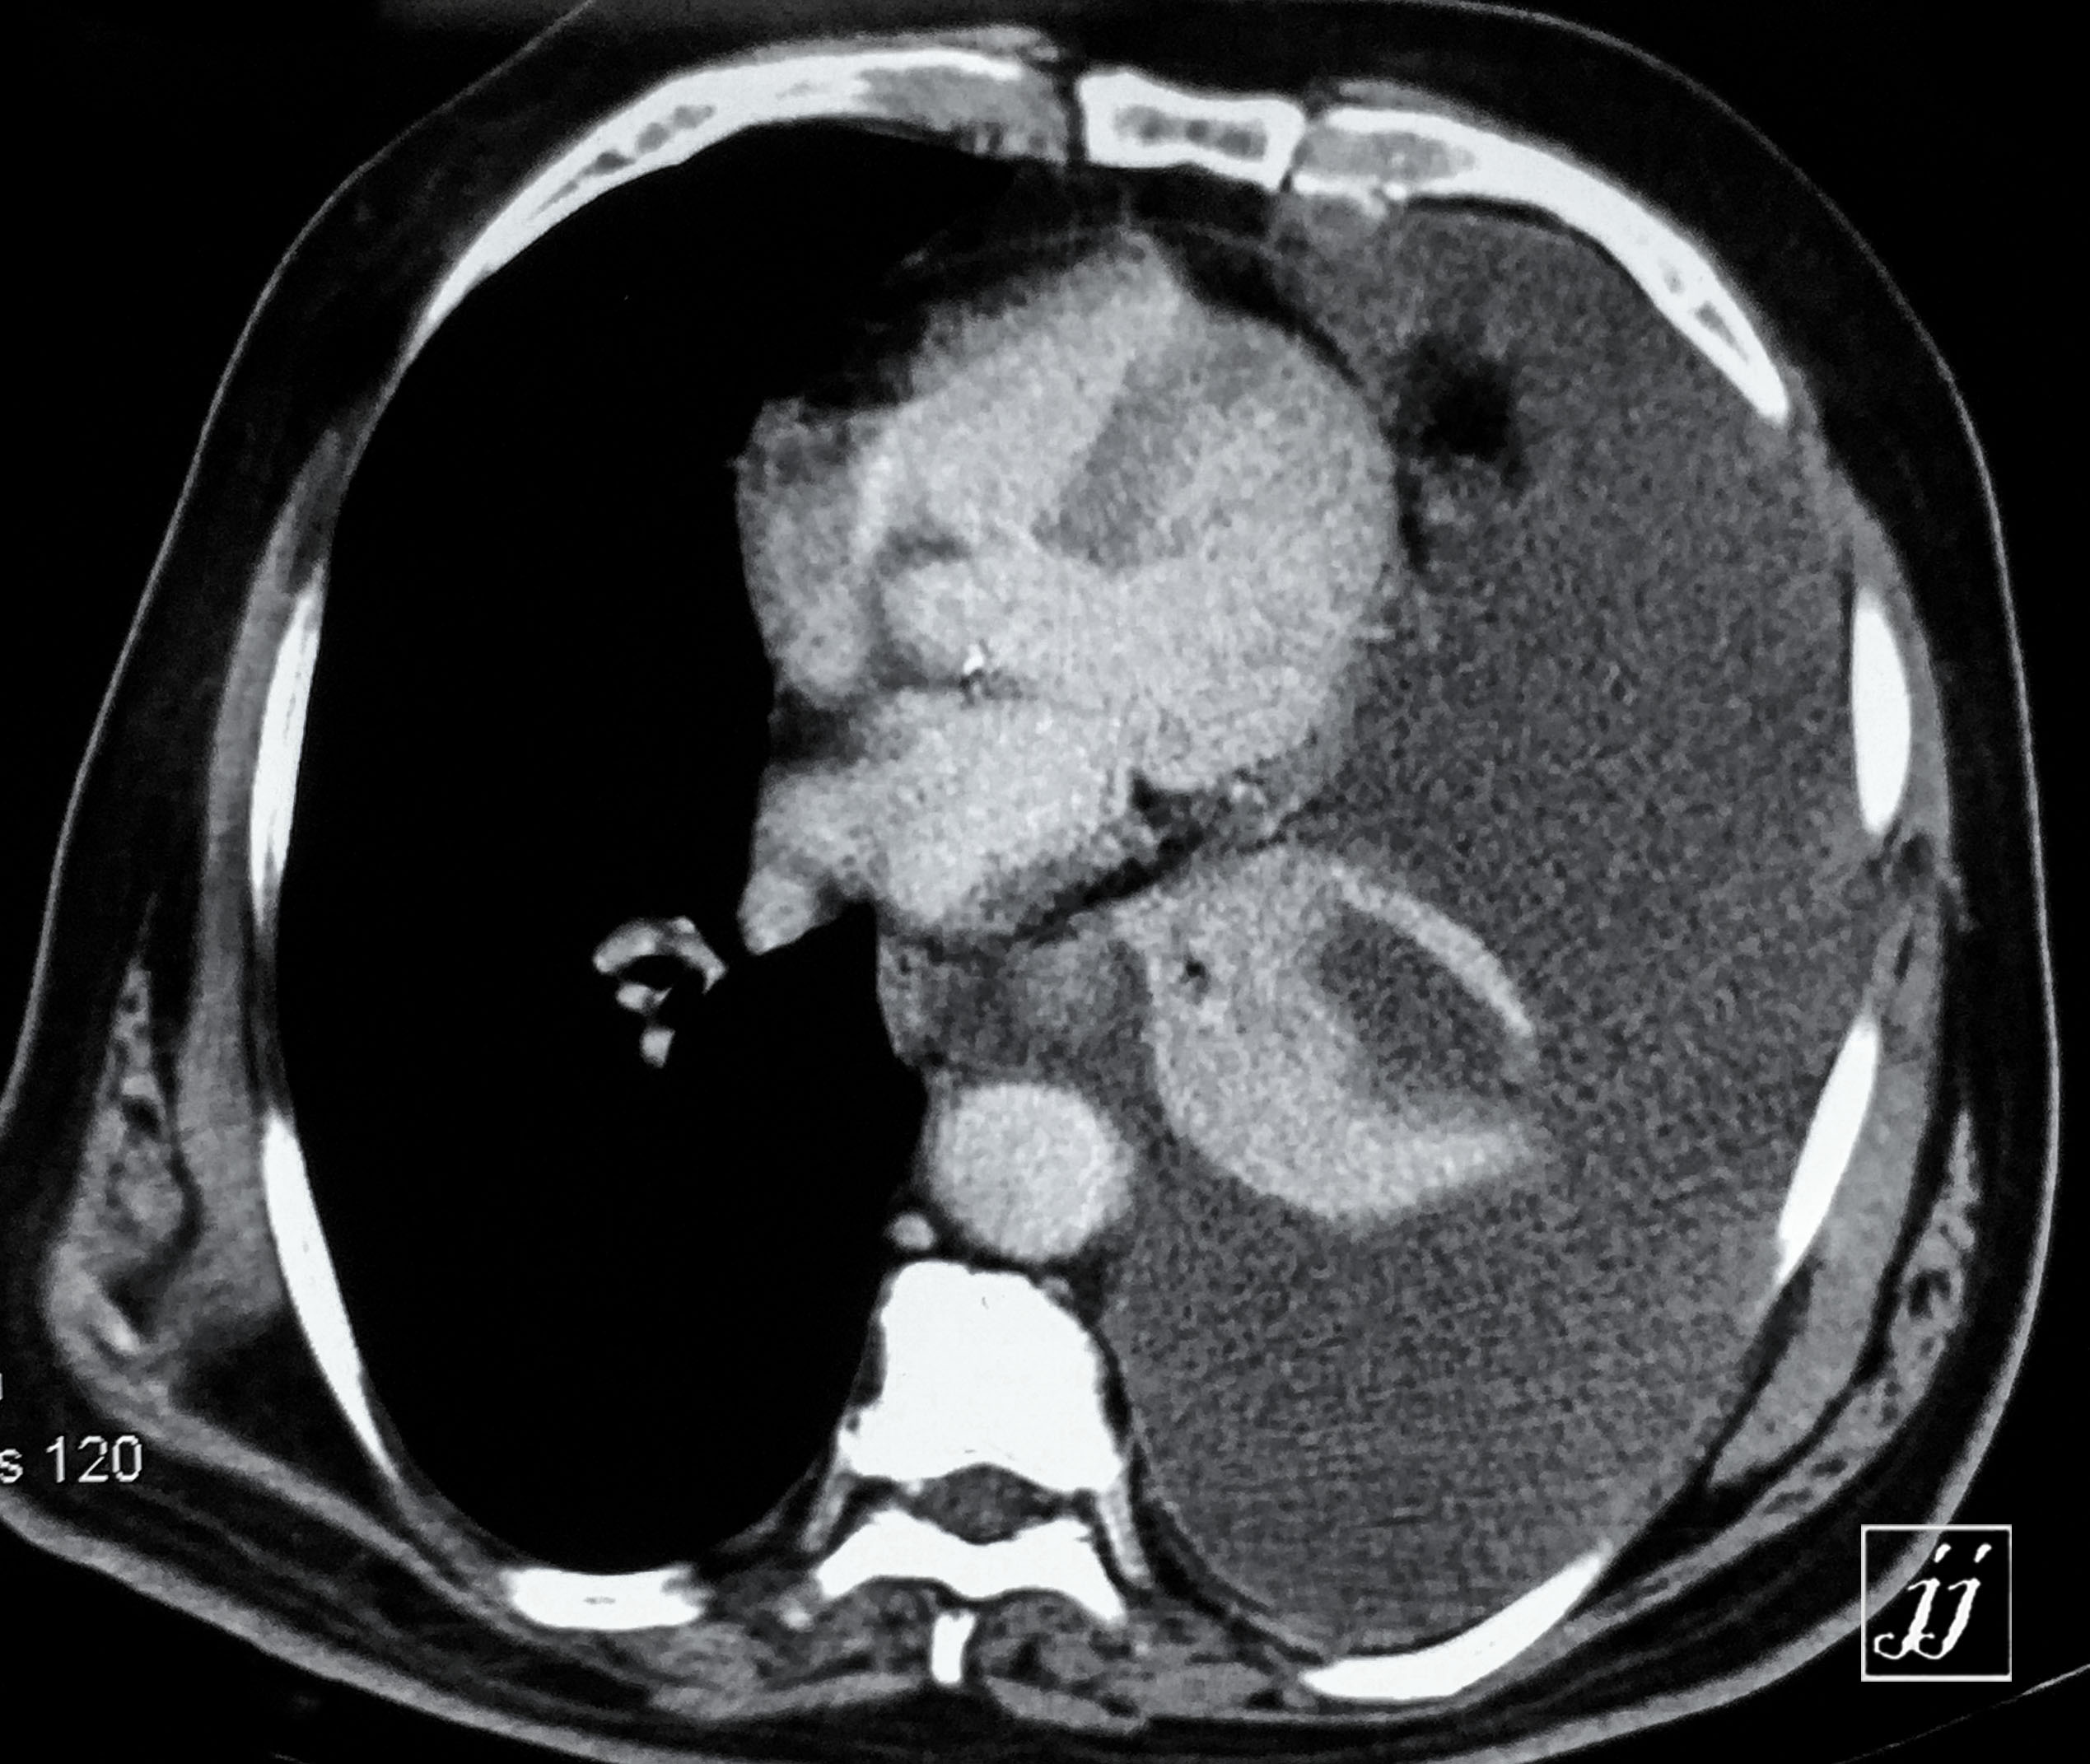

Abdomen- left side plural effusion (5)